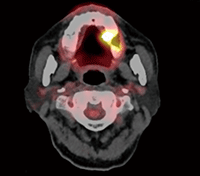

前医にてステロイド軟膏が処方され、約1ヵ月間にわたり経過観察が行われていたが、改善が得られなかったことから単純な褥瘡性潰瘍ではなく腫瘍性疾患を疑い、局所麻酔下に生検を施行した。病理組織学的に扁平上皮癌の診断を得たため、各種画像検査(MRI、FDG-PET/CT:図3)を施行してステージングを行い、左側上顎歯肉扁平上皮癌(cT2N0M0)と診断した。生検組織像(内向性で浸潤傾向が強い、YK3C)、年齢、基礎疾患を考慮し、全身麻酔下で左側上顎骨部分切除術および予防的な肩甲舌骨筋上頸部郭清術を施行した。

図❸ 術前のFDG-PET/CT画像